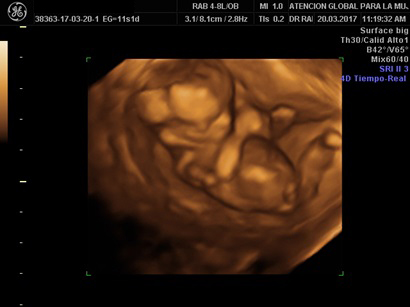

Ultrasonidos de Primer Trimeste

Se realiza una revisión estructural temprana del feto. Adicionalmente, con la aplicación de las pruebas bioquímicas en suero materno (dúo, triple, cuádruple y quíntuple marcador) a través de una simple muestra de sangre, se examinan los niveles de proteínas de origen fetal y placentario en el suero materno como marcadores para estimar un riesgo en la presentación de algún defecto cromosomático.

Se realiza entre las semanas 11 a 13.6 semanas de gestación

• Detección de enfermedades cromosomáticas como el Síndrome de Down, hasta un 95%.

• Predice enfermdades como Preeclampsia, Prematures, Restricción de Crecimiento intrauterino.